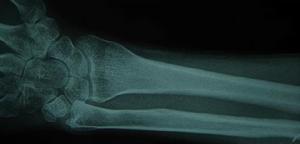

前臂外傷後疼痛活動障礙,X線片可明確骨折類型及移位情況。照片應包括肘腕關節,以了解有無鏇轉移位及上下尺橈關節脫位。

尺橈骨幹骨折本病根據其外傷病史及臨床表現可以初步確診,但還應使用一些輔助檢查的方法幫助進一步診斷,X線片可明確骨折類型及移位情況。照片應包括肘、腕關節,以了解有無鏇轉移位及上、下尺橈關節脫位。